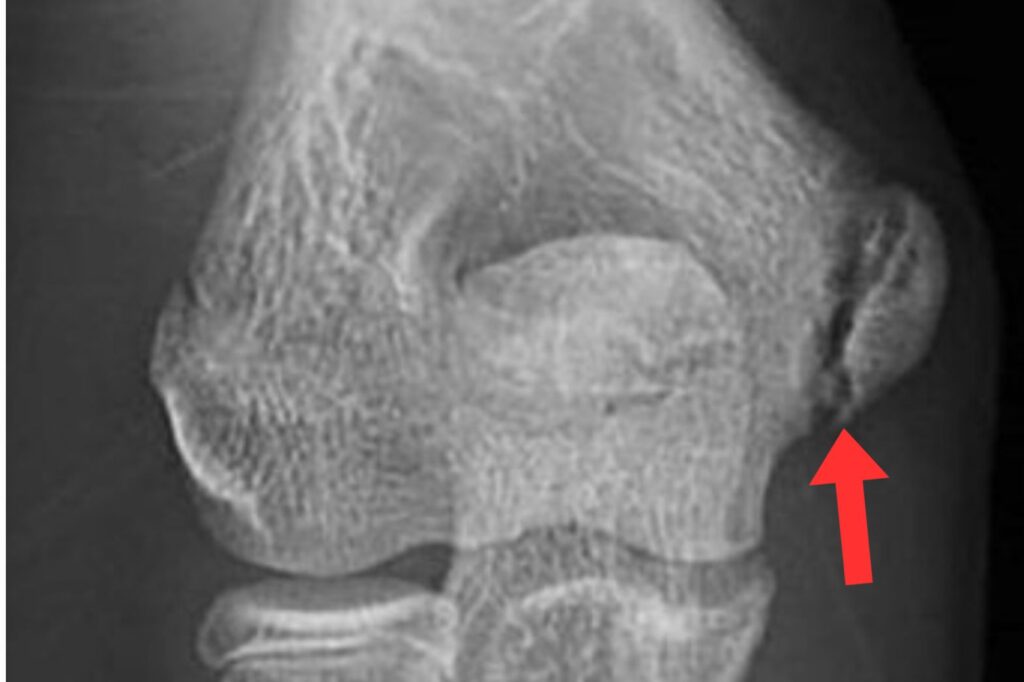

肘の外側のケガ(上腕骨小頭骨軟骨炎)

肘の外側の骨や軟骨が傷み、はがれてしまう状態です。

10代野球選手の[2〜4%]程度にみられるとされています。

初期は痛みが出にくく、

- 肘が伸びきらない

- 引っかかる感じがする

といった症状がサインになることもあります。